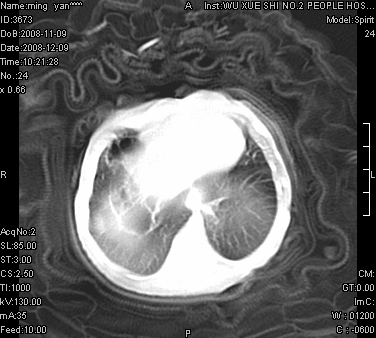

女.30天.咳嗽.喘3天.系三胞胎

考虑右肺下叶先天性肺囊肿,不除外合并右中叶肺发育不全

伴双肺感染

考虑右肺下叶先天性多发性肺囊肿可能。

考虑右肺下叶肺囊肿伴感染,右中叶节段实变或发育不全

这是一个先天性囊性腺瘤样畸形(congenital cystic adenomatid malformation,ccam),属于先天性肺发育异常,最近国外文献重新命名为先天性肺气道畸形(congenital pulmonary airway malformation,cpam),根据发生部位和畸形组织与气管、支气管的关系分成五型。本病以1岁以下婴儿多见,男性多于女性。病因为终末呼吸单元的异常增殖,形成多囊状结构。国内根据影响和病理表现分三型:ⅰ型为单个或多个大囊肿,直径大于2cm;ⅱ型为多个小囊肿,直径小于2cm;ⅲ型为大的非囊肿性病变,但显微镜下观察可见肿块由多发小囊组成(直径小于2mm)。本病可发生于肺内任何一部分,单侧肺占95%,中叶病变相对较少。

考虑右肺下叶先天性肺囊肿;右肺中叶节段性肺不张或发育不全。